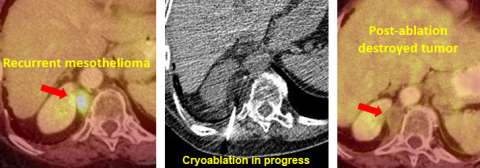

Traditional mesothelioma treatment may include surgery, radiation, and chemotherapy. At UCLA, we have established a working group to manage recurrent mesothelioma with minimal invasive image guided cryoablation. Using this technique, up to 90% of local recurrent tumors can be controlled with limited complications.